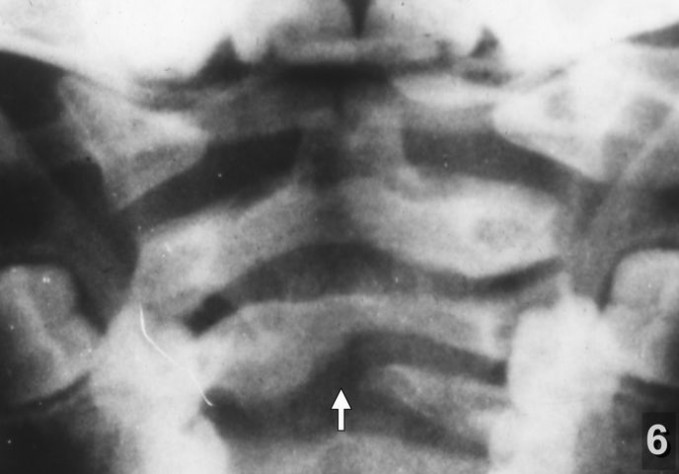

Хочу обратить внимание на следующее немаловажное обстоятельство. У детей с клиническими проявлениями последствий родовых травм шейного отдела уже с дошкольного возраста при рентгенографии наряду с симптомами перенесённых повреждений позвоночника нередко обнаруживался так называемый "спондилёз" - разрастание костных шипов (остеофитов) по краям тел позвонков (рентгенограмма 7) - признак хронического дегенеративно-дистрофического заболевания позвоночника, диагностируемого чаще всего после 40-50 лет. У взрослых при локализации процесса в шейном отделе характерными его проявлениями являются стойкий болевой синдром в шее, плечевом поясе, а также выраженные сосудистые нарушения головного мозга. В моих наблюдениях костные шипы на рентгенограммах у детей чаще всего обнаруживались в области I и II шейных позвонков (рентгенограмма 8 ) и являлись причиной упорных головных болей, острых нарушений мозгового кровообращения, "хруста" и болей в шее и другой патологии.

N-8 (306)готово" width="251" height="158" alt="Рентгенограмма 8" align="left" />Рентгенограмма 8 реб. М. 14 лет Выраженные остеофиты в области I - II шейных позвонков. Застарелый ротационный подвывих атланта.